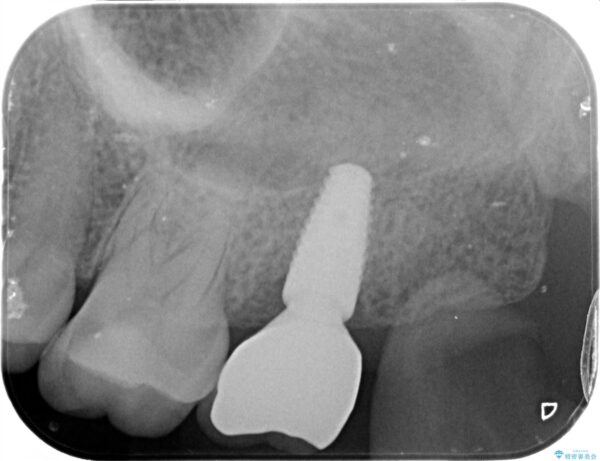

治療後

【噛むと歯が疼く】歯牙破折からのインプラント治療 治療後画像 【噛むと歯が疼く】歯牙破折からのインプラント治療 治療後画像 【噛むと歯が疼く】歯牙破折からのインプラント治療 治療後画像 【噛むと歯が疼く】歯牙破折からのインプラント治療 治療後画像